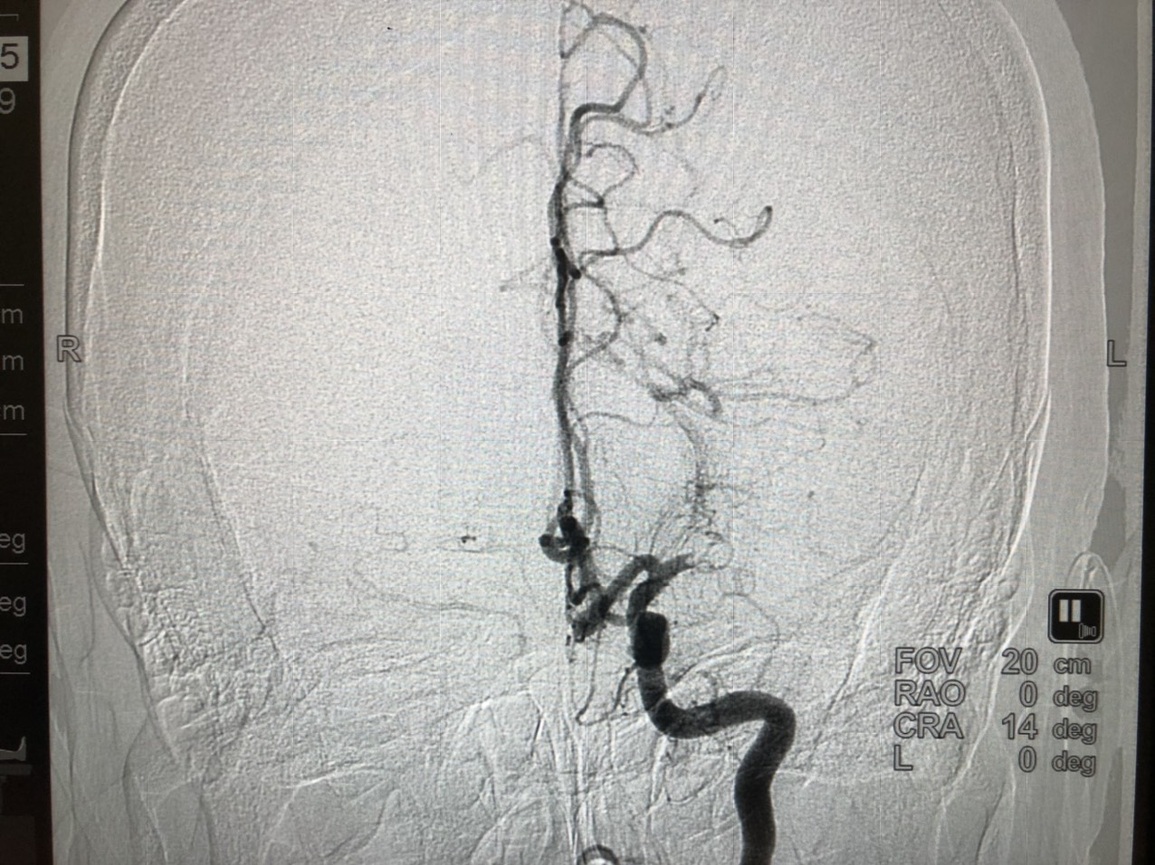

Hình ảnh tắc mạch máu não được chụp trên hệ thống chấn đoán hình ảnh DSA cao cấp của BV Vinmec Đà Nẵng.

Hình sau khi lấy cục huyết khối ra và mạch máu đã được tái thông.